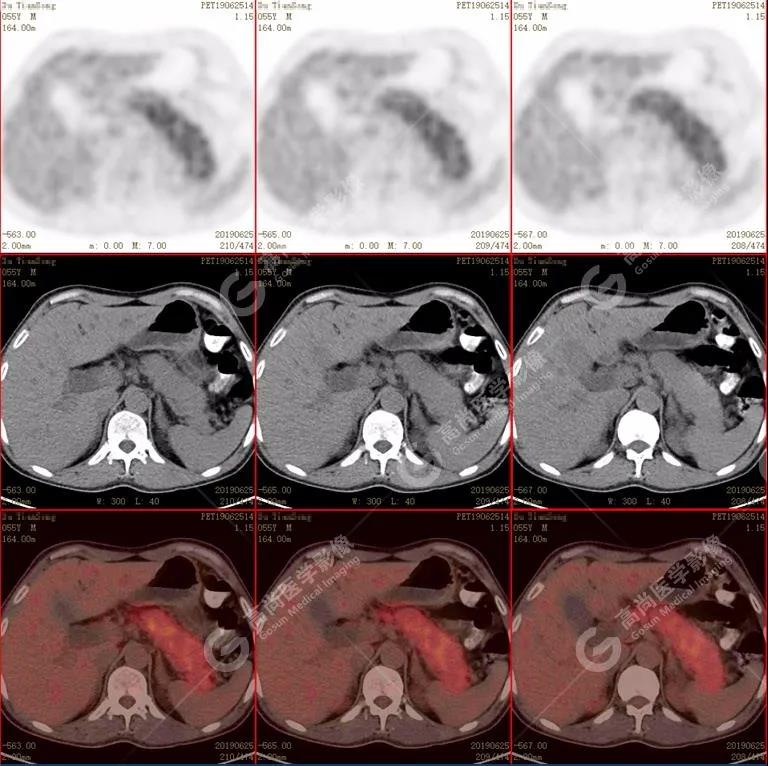

胰腺腫脹、密度均勻,代謝彌漫性不均勻增高,SUV最大值5.2 平均值4.0

(1)胰腺輕度腫脹,胰腺體尾部胰管狹窄,未見(jiàn)明顯占位性病變,代謝彌漫性增高。